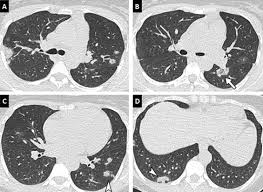

Comment Je Fais Un Scanner Simple Energie Pour Embolie Pulmonaire Aigue Epa

Comment Je Fais Un Scanner Simple Energie Pour Embolie Pulmonaire Aigue Epa from www.elsevier.com

Une irm thoracique sans injection (figure 4) effectuée à titre complémentaire a mis en évidence cette même masse paravertébrale bilatérale hétérogène la myélofibrose pouvait aussi être discutée du fait de la haute densité osseuse au scanner, mais il n'y avait aucun argument biologique en ce sens. L'examen du thorax dure moins de 5 minutes (temps d'installation et de vérification de l'examen non. Le scanner est l'examen de base. Survient dans 18% des traumatismes de la rate. Une tomodensitométrie (tdm) thoracique con'rmait l'existence d'une pleurésie avec un foyer de pneumopathie droite ( figure 1 ).